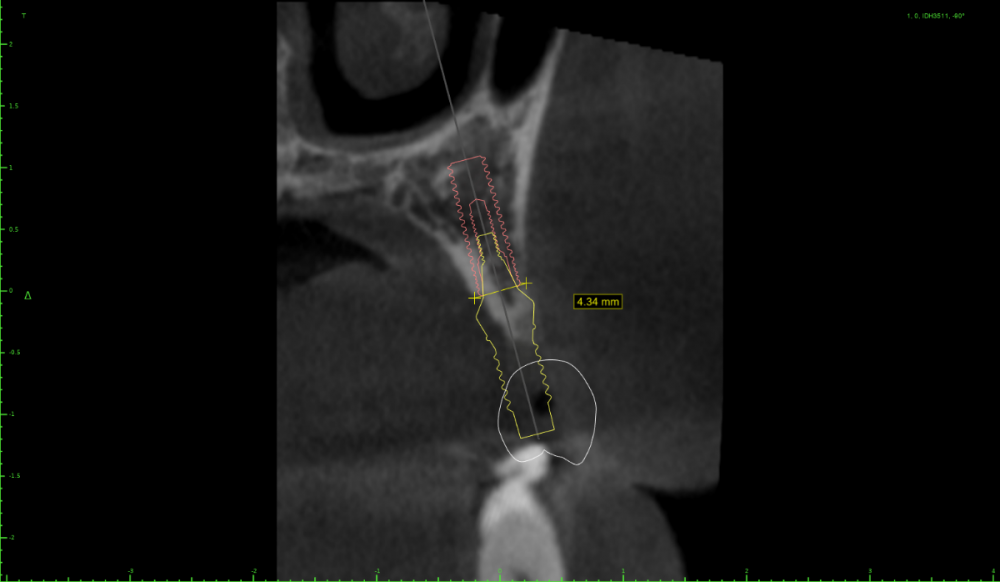

Женька Опубликовано 15 июля, 2022 Поделиться Опубликовано 15 июля, 2022 Коллеги, здравствуйте. Планирую небольшую НКР совместно с ОСЛ в боковом отделе верхней челюсти справа. Вот скрины. На реформате 3д план. Пожалуйста, поделитесь правильно ли мной выбран дизайн лоскута и фиксация мембраны (мембрана будет Creos, кость ауто+ксено (возможно ещё немного алло) p.s вариант обойтись без пластики не предлагать.)) Правильной ортопедической позиции добиться без нкр не выходит, кмк. Да и надо же пробовать как-то. Ссылка на комментарий

stommm Опубликовано 16 июля, 2022 Поделиться Опубликовано 16 июля, 2022 Если уж делать так, то я бы продлил разрез дальше, за 7. Удобнее мобилизовать, ну и медиальный сдвиг лоскута можно сделать. Мембрана 20х30. Дистальный пин на уровне 17, медиальный между 13 и 12. В области синуса пиниться стоит аккуратнее, можно провалиться, по этой же причине не стоит увлекаться работой со скребком в предполагаемой зоне фиксации мембраны. П.с. Померьте расстоянием между коронками. По наклону 17 есть ощущение что места маловато. Иногда в таких случаях проще поставить вертикально 16 ,15 с консолью 14, а не дистально наклонять апексы 16 и 14 1 Ссылка на комментарий

Женька Опубликовано 19 июля, 2022 Автор Поделиться Опубликовано 19 июля, 2022 @колесников считаете что надо именно так и обойтись без сосиджов? Мне кажется, что всё-таки более правильная позиция вот такая. . Касаемо ЗСЛ и одномоментной имплантации. Торкнуть конечно бикортикально можно, но глубить всё равно нужно. Я 4 месяца назад так поставил уже, теперь проблемы с высотой, которые я не знаю как решить пока (самое печальное, что сам же дурень создал их себе). Поэтому мне проще воплотить ОСЛ в данном случае и отсрочено поставить винты. Одно чудо за один раз, как говорится. Ссылка на комментарий